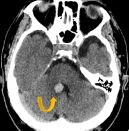

鞍内脑海绵状血管瘤案例,颅内出血在磁共振成像(MRI)上具有特征性表现,包括T1加权像上的等强度、T2加权像上的高强度和鞍区钆增强T1加权像上的弥散均匀强化。在这篇报告中,我们提...